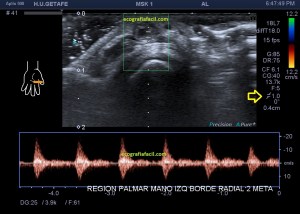

El paciente del caso que te expongo hoy como primer post del 2021 es un paciente de uno 40 años que nota desde hace un año un pequeño bultoma en la palma de la mano, en la región flexora en el eje largo del 2 dedo, a la altura de la articulación metacarpofalángica, ligeramente radial, viene referido del traumatólogo.

En mi interrogatorio habitual el paciente descarta traumatismo, no recuerda, ligero crecimiento sin dolor. Al tocar el bulto para localizarlo, lo primero que me llama la atención es que tiene pulso, muy evidente, es duro y muy pequeño, pero el pulso es muy evidente, no había coloración cutánea. El paciente ni el médico refirieron este dato superimportante (el latido) que dirigió el estudio absolutamente, como ves en la imágenes.

Escojo la sonda de ultraalta frecuencia, 18 mHz, y ajusto los parámetros para realizar un estudio con la intención de encontrar algo muy superficial, por supuesto, gran cantidad de gel, nada de presión, apoyo levemente el transductor.

1

En esta primera imagen me encuentro, primero, un estructura heterogénea, redonda, ligeramente ovalada con un centro anecoico y un halo grueso e hipoecogénico.

En la imagen 5 ves el típico aspecto de un vaso de alto flujo, lo normal, ya que tenía latido. Vas a ver dicho espectro con aspecto de picos y valles muy marcados, el sonido también es diferencial, puedes ver el doppler espectral y escucharlo. Su sonido y su aspecto es distinto del de una vena.

En este caso debí usar una muestra, flecha amarilla de la imagen 5, lo más pequeña posible, ya que el vaso lo era igual, adaptaremos esta muestra al tamaño del vaso que quieras estudiar. si la muestra no es la idónea la lectura puede ser incoherente. La muestra es el tamaño del «roi2 que hará el registro de la zona a estudio. Te enlazo arriba para que revises nociones básicas de doppler en post anteriores, también puedes consultar el índice del blog al final de este Post.

El diagnóstico final del radiólogo fue psudoaneurisma de la arteria palmar del segundo dedo.